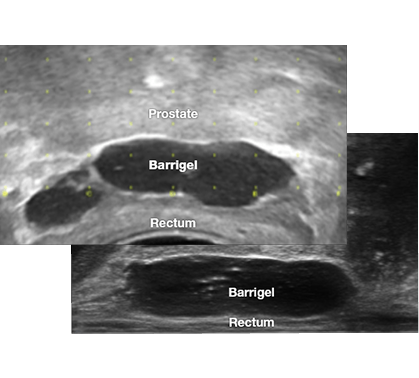

Highly visible on TRUS. Image-guided procedure with real-time placement visualization.1,4-6